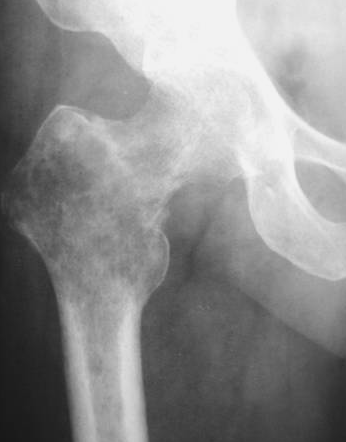

▌膨胀性破坏

膨胀性破坏是地图样破坏的特殊形式,影像学表现为骨质破坏区骨膨胀,周围可见不同程度扩张的骨壳(图 5、图 6、图 7、图 8)。膨胀性破坏是由于肿瘤从骨皮质内面破坏,骨外膜增生形成新生骨造成膨胀的。引起膨胀性破坏见于大多数良性肿瘤和肿瘤样病变如单纯性骨囊肿,动脉瘤样骨囊肿、内生软骨瘤和软骨粘液纤维瘤等,少数也可见于恶性肿瘤如转移瘤、骨髓瘤等。

图 6.膨胀性破坏:骨巨细胞瘤